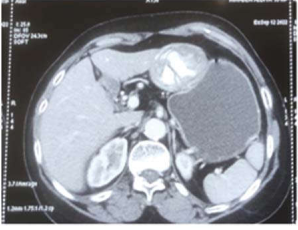

Well-defined exophytic mass found protruding from the left lobe of the liver.

Description: No description available.

: CECT:A well-defined exophytic non-enhancing lesion of size 57x50x49 mm is noted in the left lobe of the liver with Irregular calcified membranes noted within the lesion